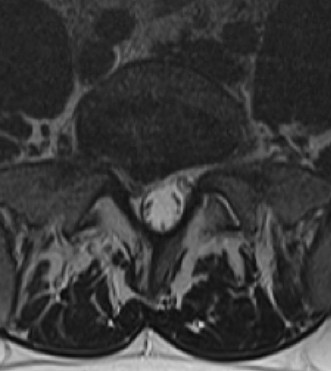

CASE 1 A 63-year-old male sustained a hyperextension injury to his neck while diving into a pool. Upon presentation, he reports decreased sensation in his hands and decreased strength in his arms and wrists, but no lower extremity complaints. On motor examination, he has 5/5 strength in his deltoids and elbow flexors and 4/5 strength in the elbow extensors, wrist extensors, and finger flexors. Lower extremity motor examination is normal. Sensation is decreased to light touch in both hands. Otherwise his sensation is preserved. Images of his cervical spine are shown in Figures 1–1 to 1–3.

Figure 1–1

The correct answer is (B). The clinical scenario describes a patient with central cord syndrome (CCS). CCS continues to be the most common incomplete spinal cord injury accounting for 15.7% to 25% of all spinal cord injuries. The characteristic presentation is an extension moment injury in a previously spondylotic and stenotic spine. Figures 1–1 to 1–3 demonstrate a spondylotic spine with central narrowing and CSF effacement that is worst at the C3–4 level. Bleeding, edema, and/or Wallerian degeneration lead to damage of the lateral corticospinal tract which is the main descending motor tract in the spinal cord. The more central anatomic position of the homunculus to the upper extremities places them at greater risk than those to the lower extremities. As such, injury to the lateral corticospinal tract is characterized by upper more than lower extremity involvement and motor deficits being more pronounced than sensory deficits.